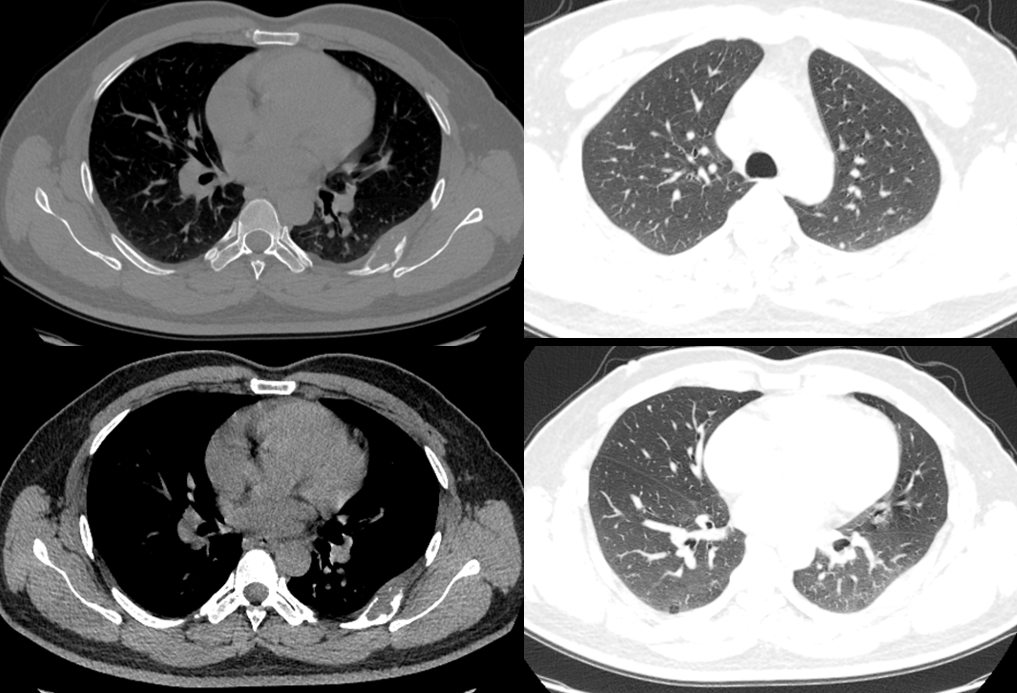

病例1

• 男,19岁

• 主诉:胸痛4天

• 现病史:患者4天前无明显诱因下出现胸口疼痛,休息时不能好转,伴胸闷气喘,活动后加重,无畏寒、发热,无咳嗽咳痰,无心悸,无恶心呕吐,无黑蒙及晕厥,无腹痛、腹泻、腹胀等症状,至当地医院就诊,查心脏彩超、 心肌酶谱+肌钙蛋白、生化指标均正常,心电图提示窦性心动过速,白细胞计数、超敏 C 反应蛋白偏高,遂予以口服抗生素治疗,具体不详,用药后上述症状无明显好转

• 既往史:2019 年于当地医院行鼻窦手术治疗,术后恢复可

• 影像检查:2023-11-04 胸部CT平扫;影像号:2992234

影像学表现

图片